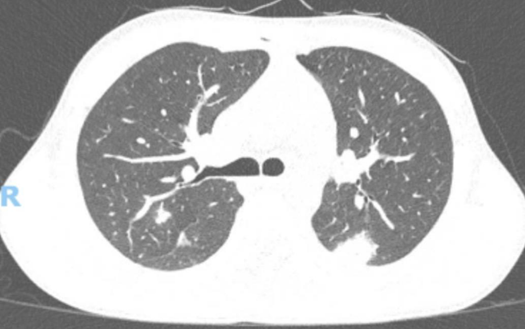

When Pulmonary Tuberculosis Leads to Pneumothorax: An Unusual Presentation

Catarina Bettencourt Giesta, Manuel d'Almeida, Sara Pires Ferreira

bjcr50